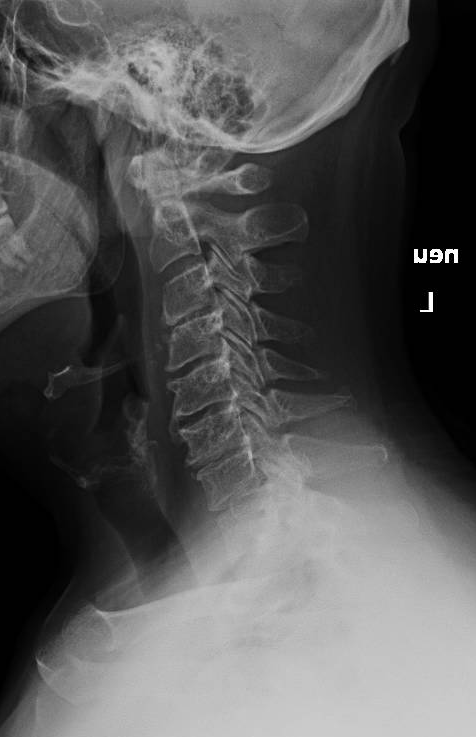

What would your surgical plan be for this patient with a cervical epidural abscess and severe arm weakness? #neurosurgery #physicaltherapy #chiropractor #spine #spinehealth #spinesurgery #cervicalspine

I performed a partial C4 corpectomy with fibular allograft -Abscesses can be more solid than expected -Partial corpectomy offers excellent decompression + stability -Material choice (titanium/allograft/autograft) matters less than thorough I&D and stabilization #cervicalspine